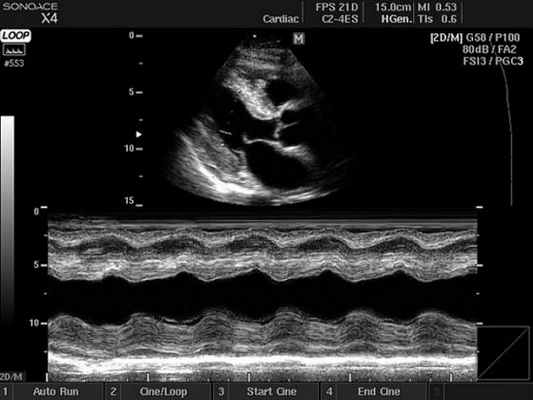

3. Импульсно-волновая допплер-ЭхоКГ. Тот же принцип усиления применим и в режиме импульсно-волнового допплеровского исследования, причем здесь он имеет особенное клиническое значение для регистрации потоков в легочных венах из апикальной позиции, для оценки диастолической функции левого желудочка.

4. Оценка коронарного резерва. Последней по порядку, но не по значимости упомянем возможность при контрастном усилении оценивать скорости потоков в коронарных артериях или в шунтах из внутренней грудной артерии, что вызывает клинический интерес в плане неинвазивной оценки коронарного резерва. С 1999 г. успешное трансторакальное измерение коронарного резерва при помощи высокочастотных датчиков и/или допплеровского контрастного усиления описано в области ПМЖВ для 90% пациентов и в области правой коронарной артерии - для 80% пациентов.